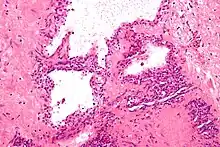

| Micrograph showing a pancreatic serous cystadenoma. H&E stain. | |

Pancreatic serous cystadenoma is a benign tumour of the pancreas.[2] It is usually solitary and found in the body or tail of the pancreas, and may be associated with von Hippel–Lindau syndrome.[2]

Pathologists classify serous cystic neoplasms into two broad groups. Those that are benign, that have not spread to other organs, are designated "serous cystadenoma".[5] Serous cystadenomas can be further sub-typed into microcystic, oligocystic (or macrocystic), solid, mixed serous-endocrine neoplasm, and VHL-associated serous cystic neoplasm. This latter classification scheme is useful because it highlights the range of appearances and the clinical associations of these neoplasms. Serous cystic neoplasms that have spread ("metastasized") to another organ are considered malignant and are designated "serous cystadenocarcinoma".

Pathology